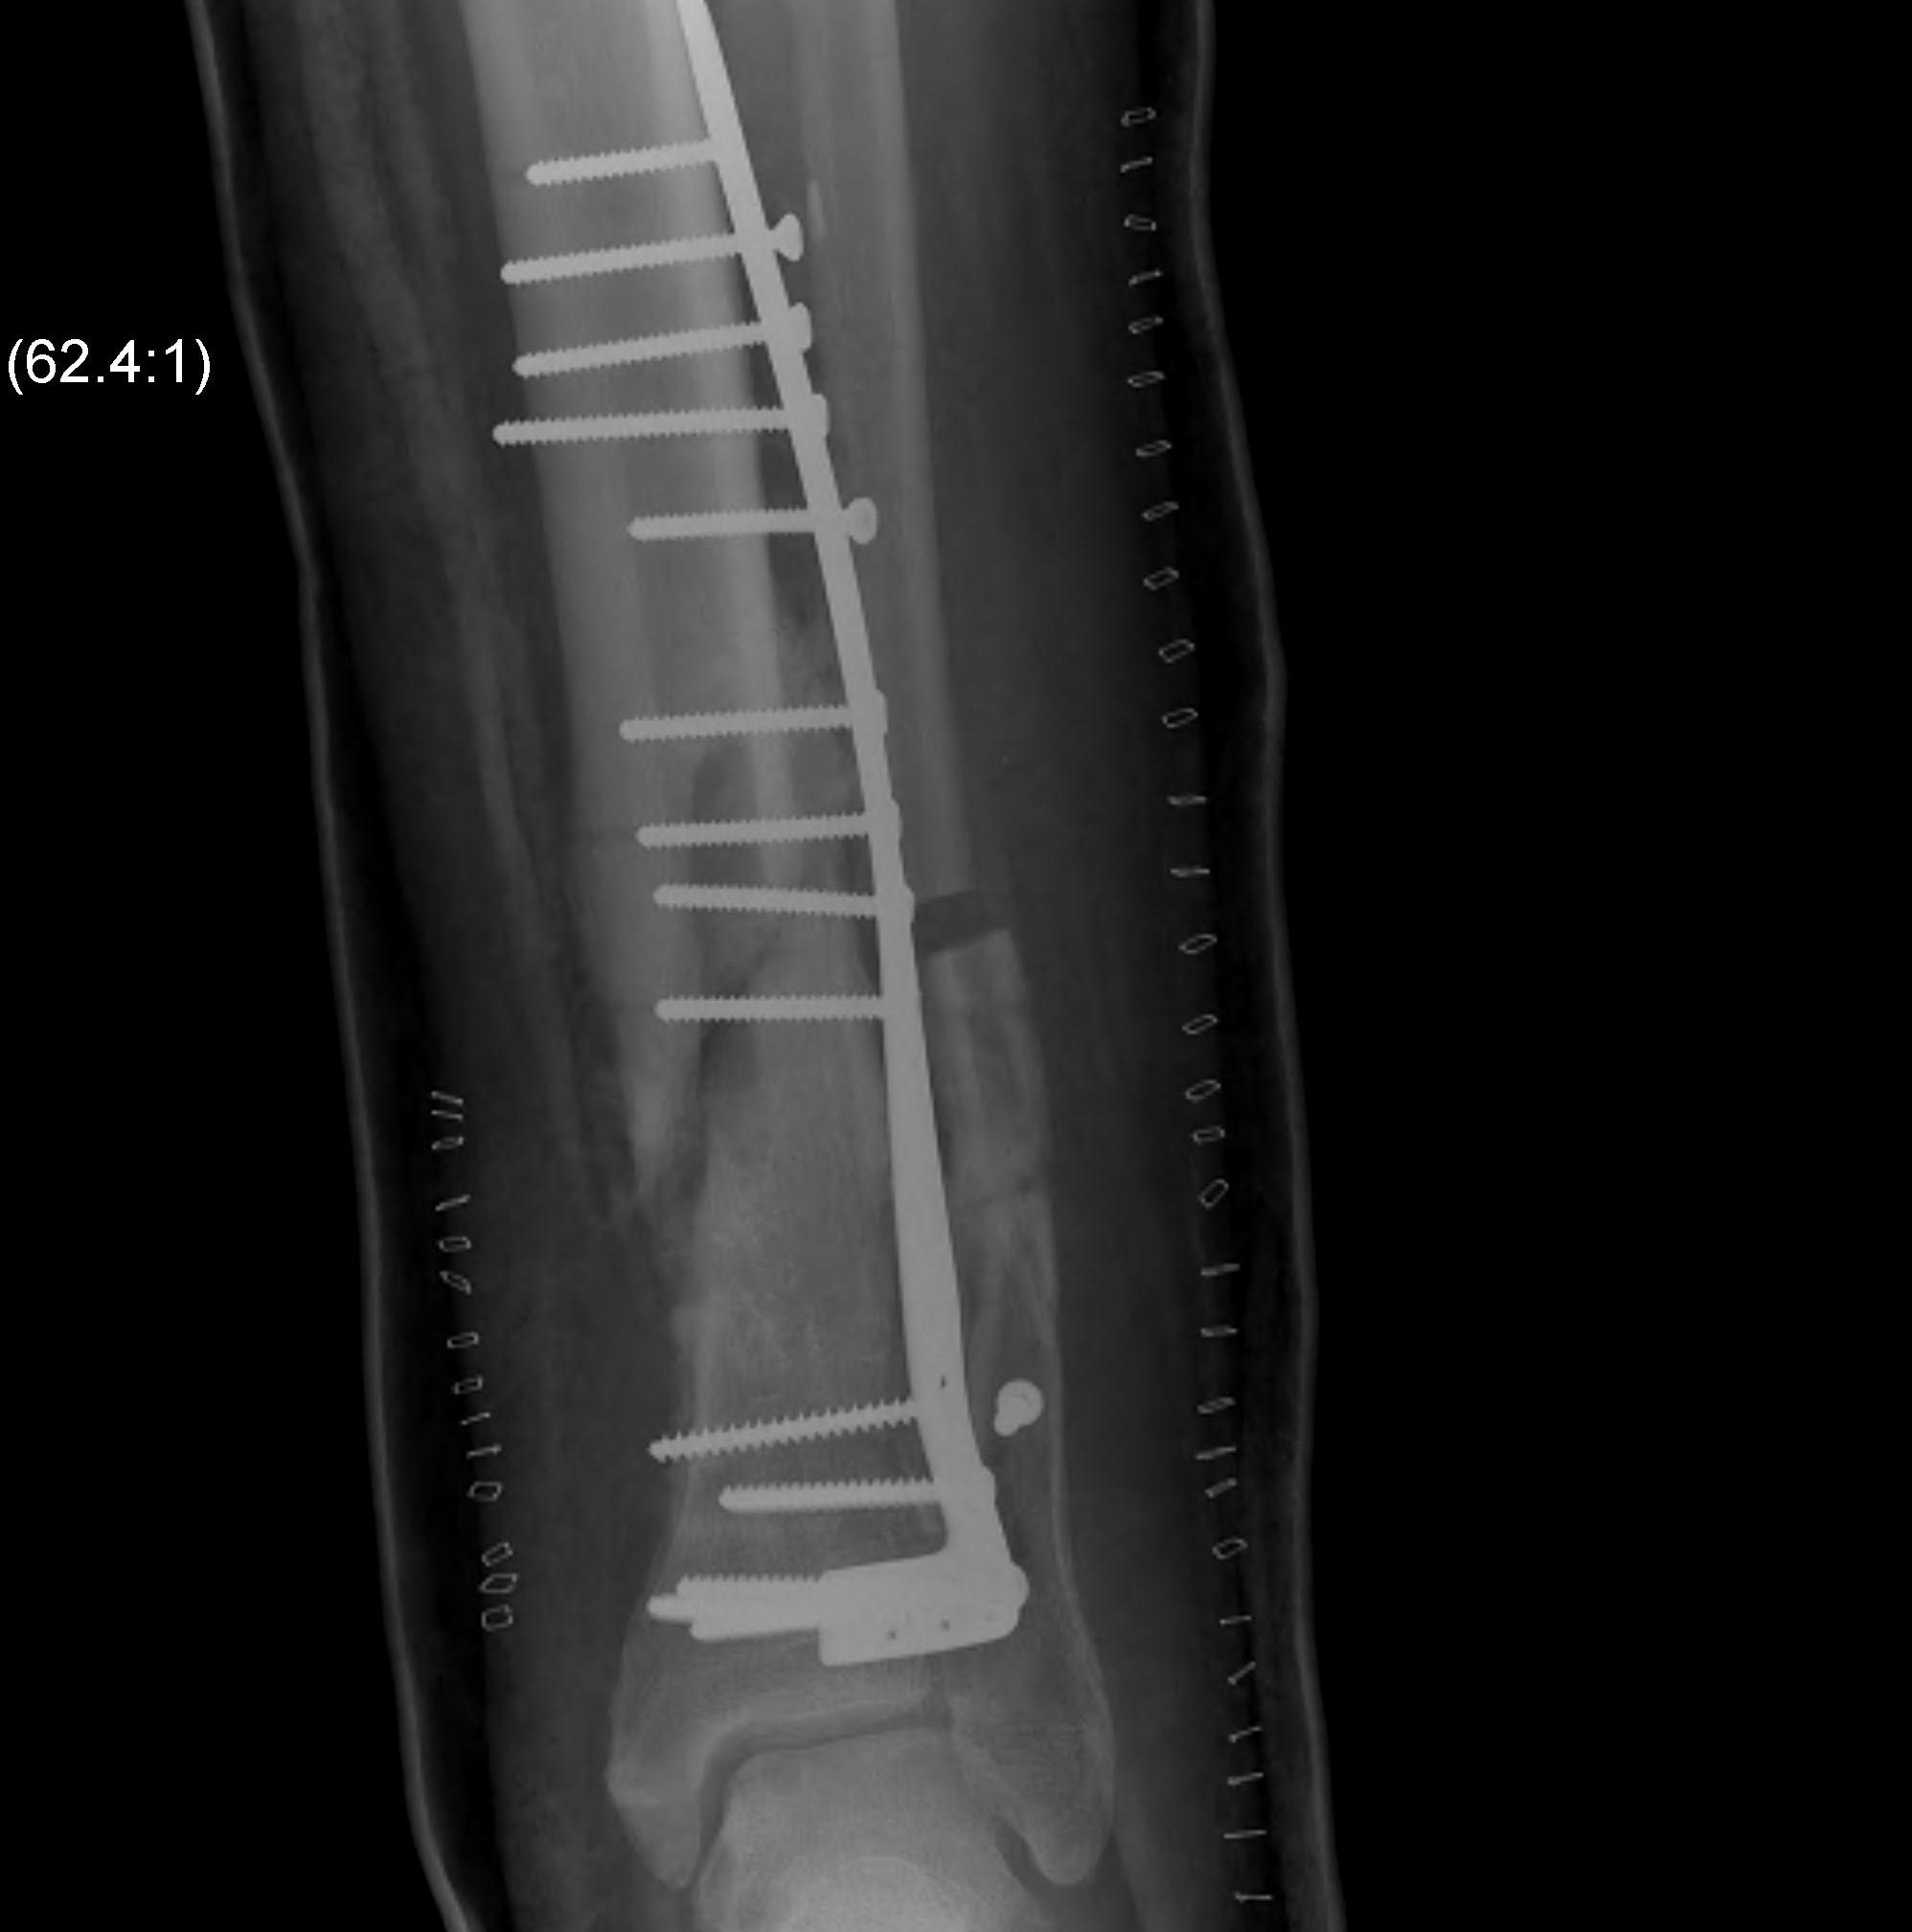

Intra-medullary Nail

Indications

- wounds / soft tissues not suitable to plate

- relatively stable

- sufficient distal bone

Design

Distal tibial nails

- multiple distal screws

- usually 2 medial-lateral and 1 AP

- most distal screw within 5 mm of end of nail

Technique

Consider semi-extended suprapatella nail

- easier to reduce fracture

- easier to get AP and lateral fluoroscopy

Most important is to centre guide wire over talus

- in lateral and AP

- use finger reduction tools and pass across fracture site to exact centre in AP and lateral

- bone reduction forceps

- blocking screws

- universal external fixation

- plate fibula